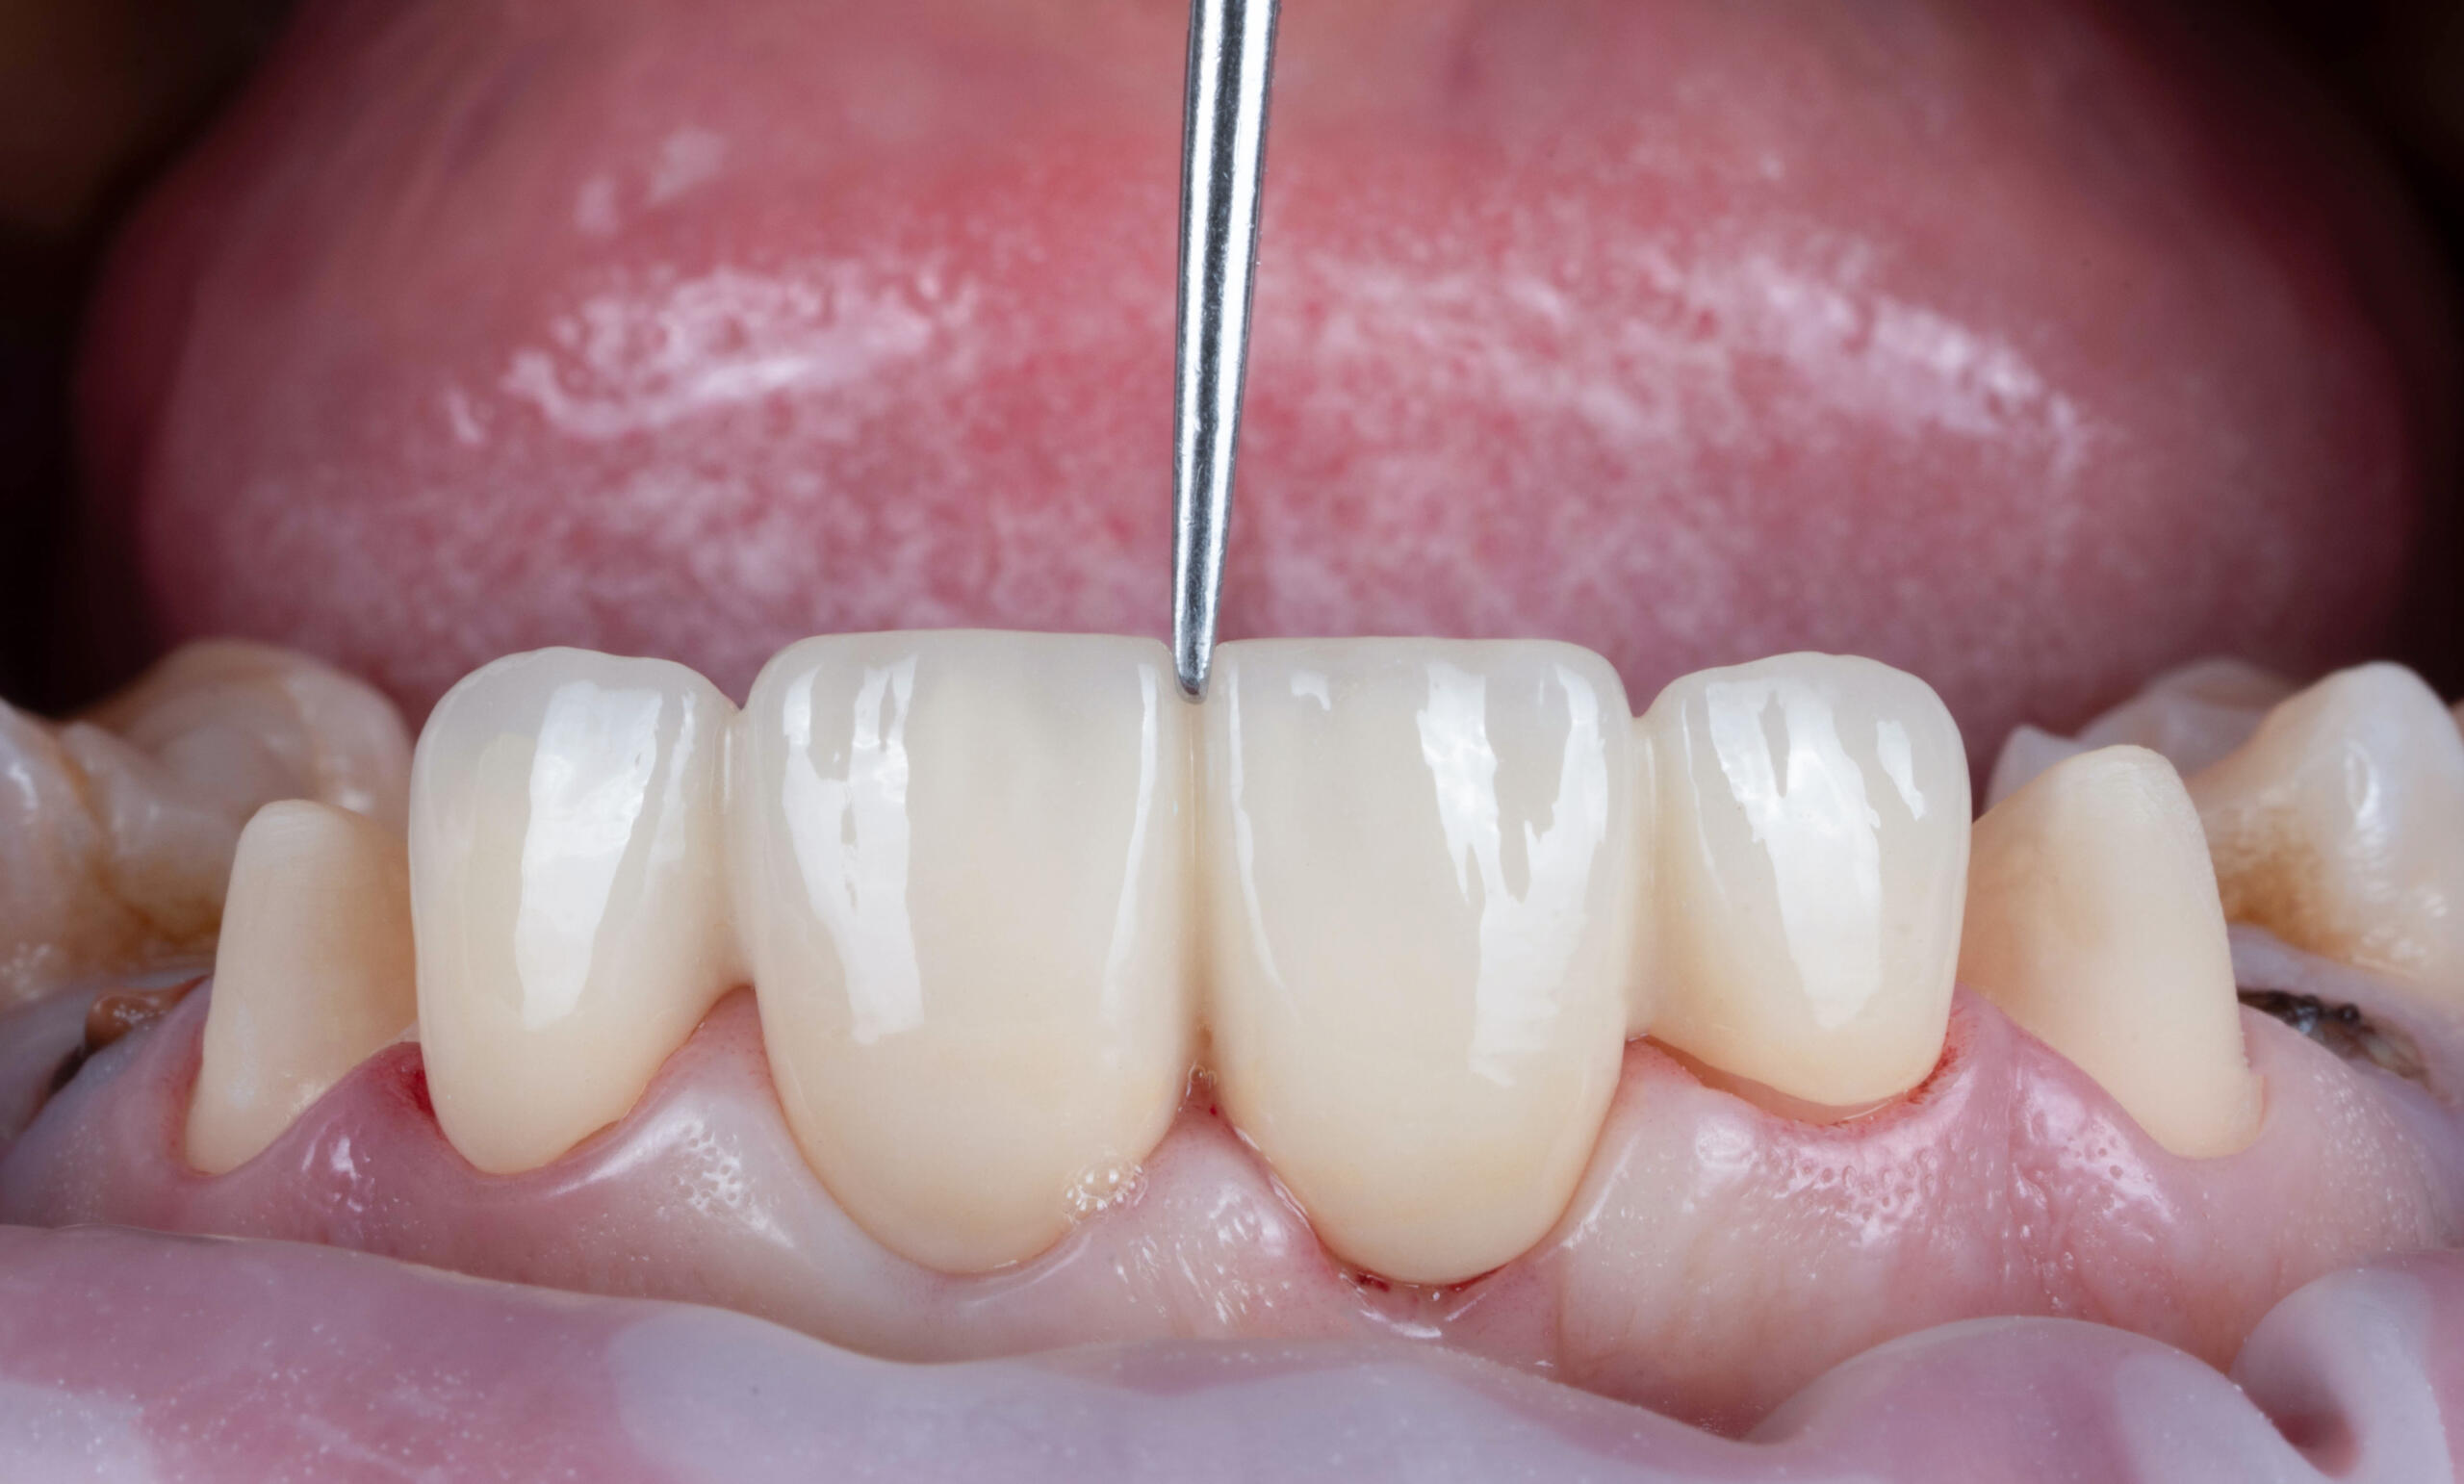

O punte dentară este o lucrare protetică fixă formată din una sau mai multe coroane dentare unite, menite să înlocuiască unul sau mai mulți dinți lipsă. Aceasta se sprijină pe dinții naturali învecinați (șlefuiți și acoperiți cu coroane) sau pe implanturi dentare în funcție de caz.

- Proba lucrării și adaptarea funcțională și estetică

- Fixarea definitivă cu ciment special